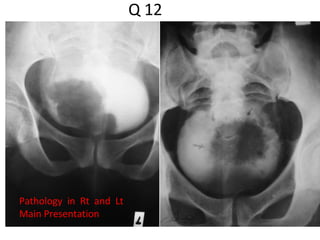

Q 12

Pathology in Rt and Lt

Main Presentation

Q 12 Pathology inRt and Lt Main Presentation